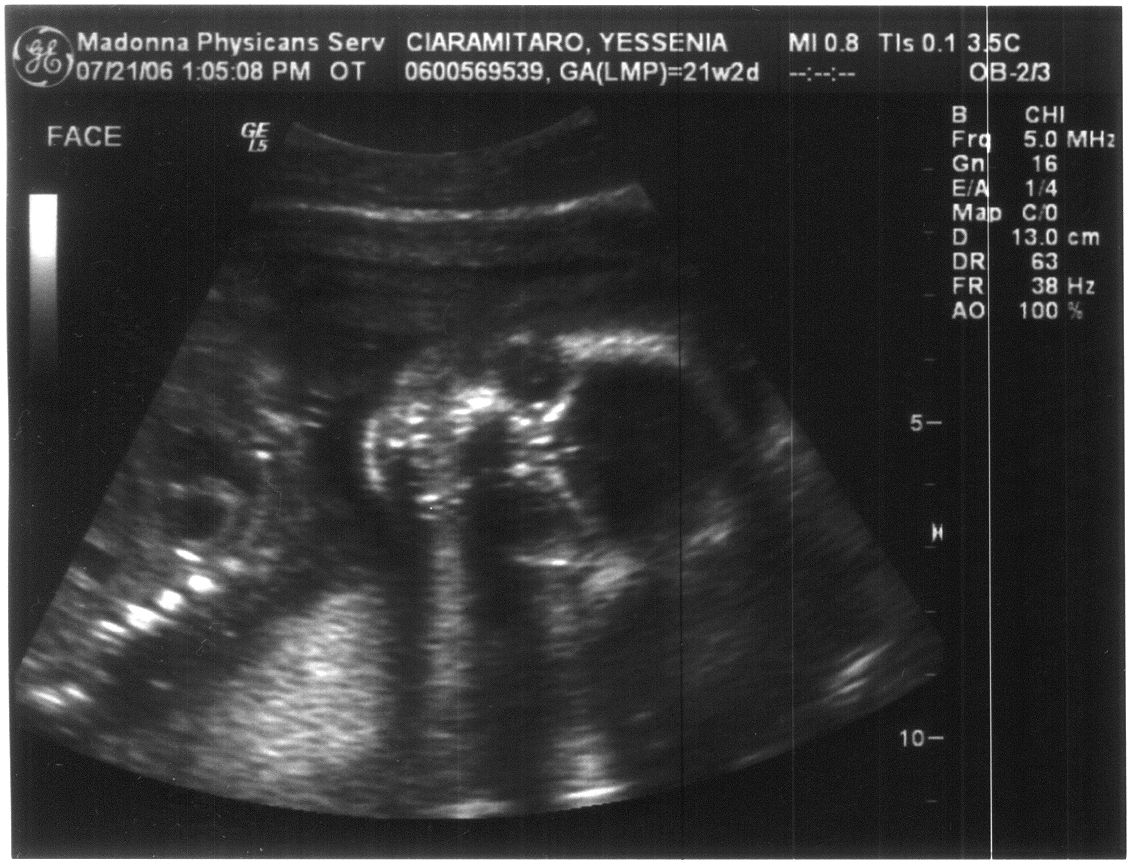

Last Modified On:March 2, 2015 5 PM Welcome to the future member of the Ciaramitaro clan!

Looks like our baby is coming bundled with a Skeleton Halloween Costume!